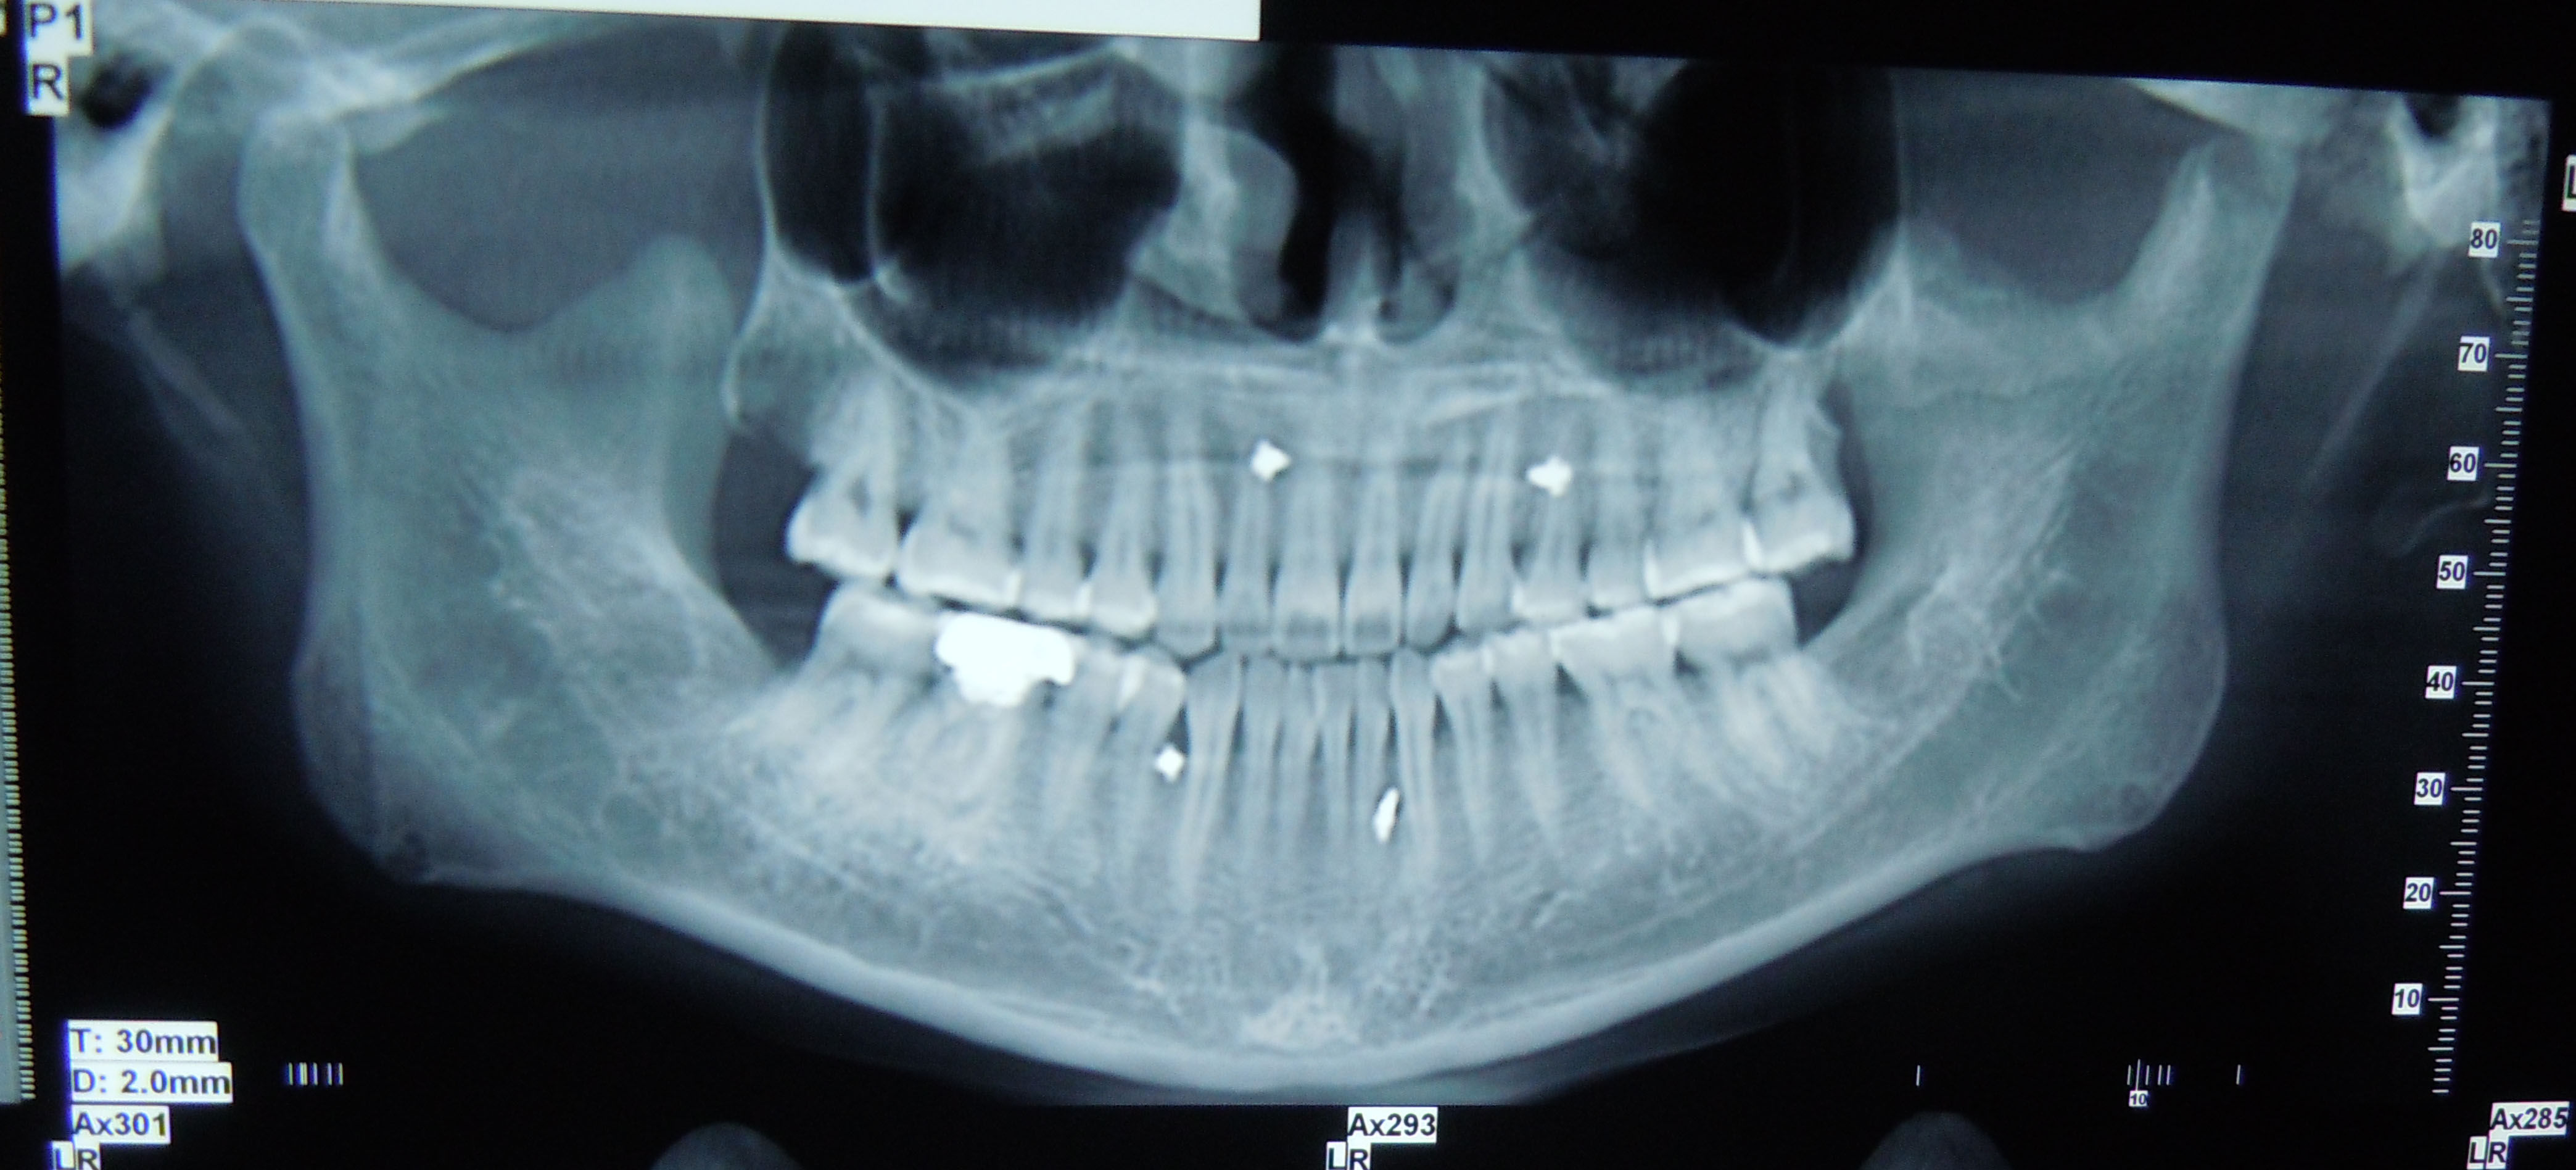

颞下颌关节脱位是指髁突滑出关节窝以外超越了关节运动的正常限度以致不能自行复回原位。多数是颞下颌关节髁突前方脱位。最主要的临床表现是闭不上嘴。辅助检查:X线片可见髁突脱位于关节结节前上方。

来我院就诊时左侧关节窝空虚,前牙反颌,偏斜

关节长期的脱臼,手法是不可能复位的,因为软组织已经充满的关节窝,关节窝内已经没有髁突的位置了。所以在手术中,我们切除关节结节和一部分髁突,这样也不能在术后复位髁突,所以我又在上下颌打上牵引钉,把下颌拉会关节窝。

手术后一个月,患者诉前牙还是反颌,经检查发现,前牙反颌的程度比原来改善,但是没有完全解决,左侧髁突没有达到关节窝的最后点,而且健侧的髁突也被拉得向前了。

要求拍CT,ct显示左侧髁突骨质改建良好,可以考虑正畸治疗这种反颌,后来我们考虑这个人都27岁了,对面容要求也不高了,而且牵引钉拉髁突向后的力量不足,是因为上下颌牙尖的锁结很厉害,所以建议戴薄稳定合垫,打开咬合,同时戴颏兜加大向后的力量,再观察一个月。